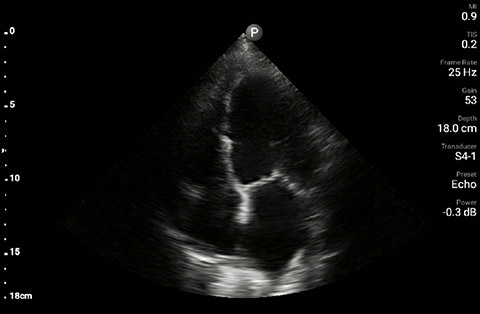

The patient had reduced LV systolic function without new or severe valvular pathology, a dilated, non-collapsing IVC, and diffuse B lines (left greater than right) on lung ultrasound imaging.

Apical 4-chamber

Parasternal long-axis